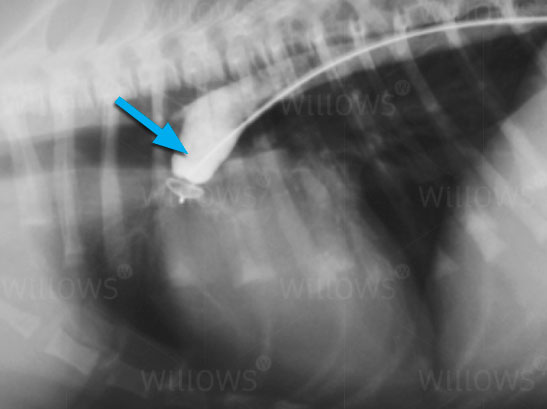

Fig 1:

There is no contrast (‘dye’) escaping past the ACDO which indicates that it is in a good position and providing complete closure.